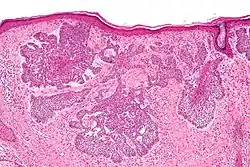

- Superficial basal-cell carcinoma, formerly referred to as in-situ basal-cell carcinoma, is characterized by a superficial proliferation of neoplastic basal-cells. This tumor is generally responsive to topical chemotherapy, such as imiquimod, or fluorouracil, although surgical treatment is better able to ensure complete removal and confirm that there is not an underlying more aggressive subtype that was not sampled in the initial biopsy.

| Cystic basal-cell carcinoma | Morphologically characterized by dome-shaped, blue-gray cystic nodules.[31]: 647 |

| Superficial basal-cell carcinoma (also known as "superficial multicentric basal-cell carcinoma") | Occurs most commonly on the trunk and appears as an erythematous patch.[30]: 748 [31]: 647 | ||